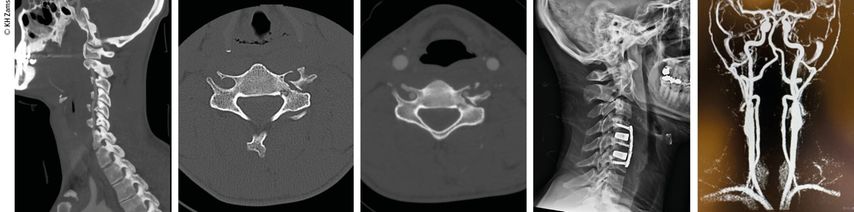

Abb. 3: Mann, 30a, Z.n. Snowboardsturz, Rotations-/Subluxationsverletzung C5/6 mit Dissektion der A. vertebralis r.; Zervikobrachialgie mit sensiblem Defizit; OP unter Heparintherapie, APT für 3 Monate

Abb. 4: Mann, 28a, Z.n. Schisturz; instabile Teardrop-Verletzung mit Dissektion A. vertebralis l.; Zervikobrachialgie mit Dysästhesie C6, mehrere kleine embolische Infarkte vertebrobasilär mit Koordinationsstörung; OP + Heparintherapie initial, anschließend APT